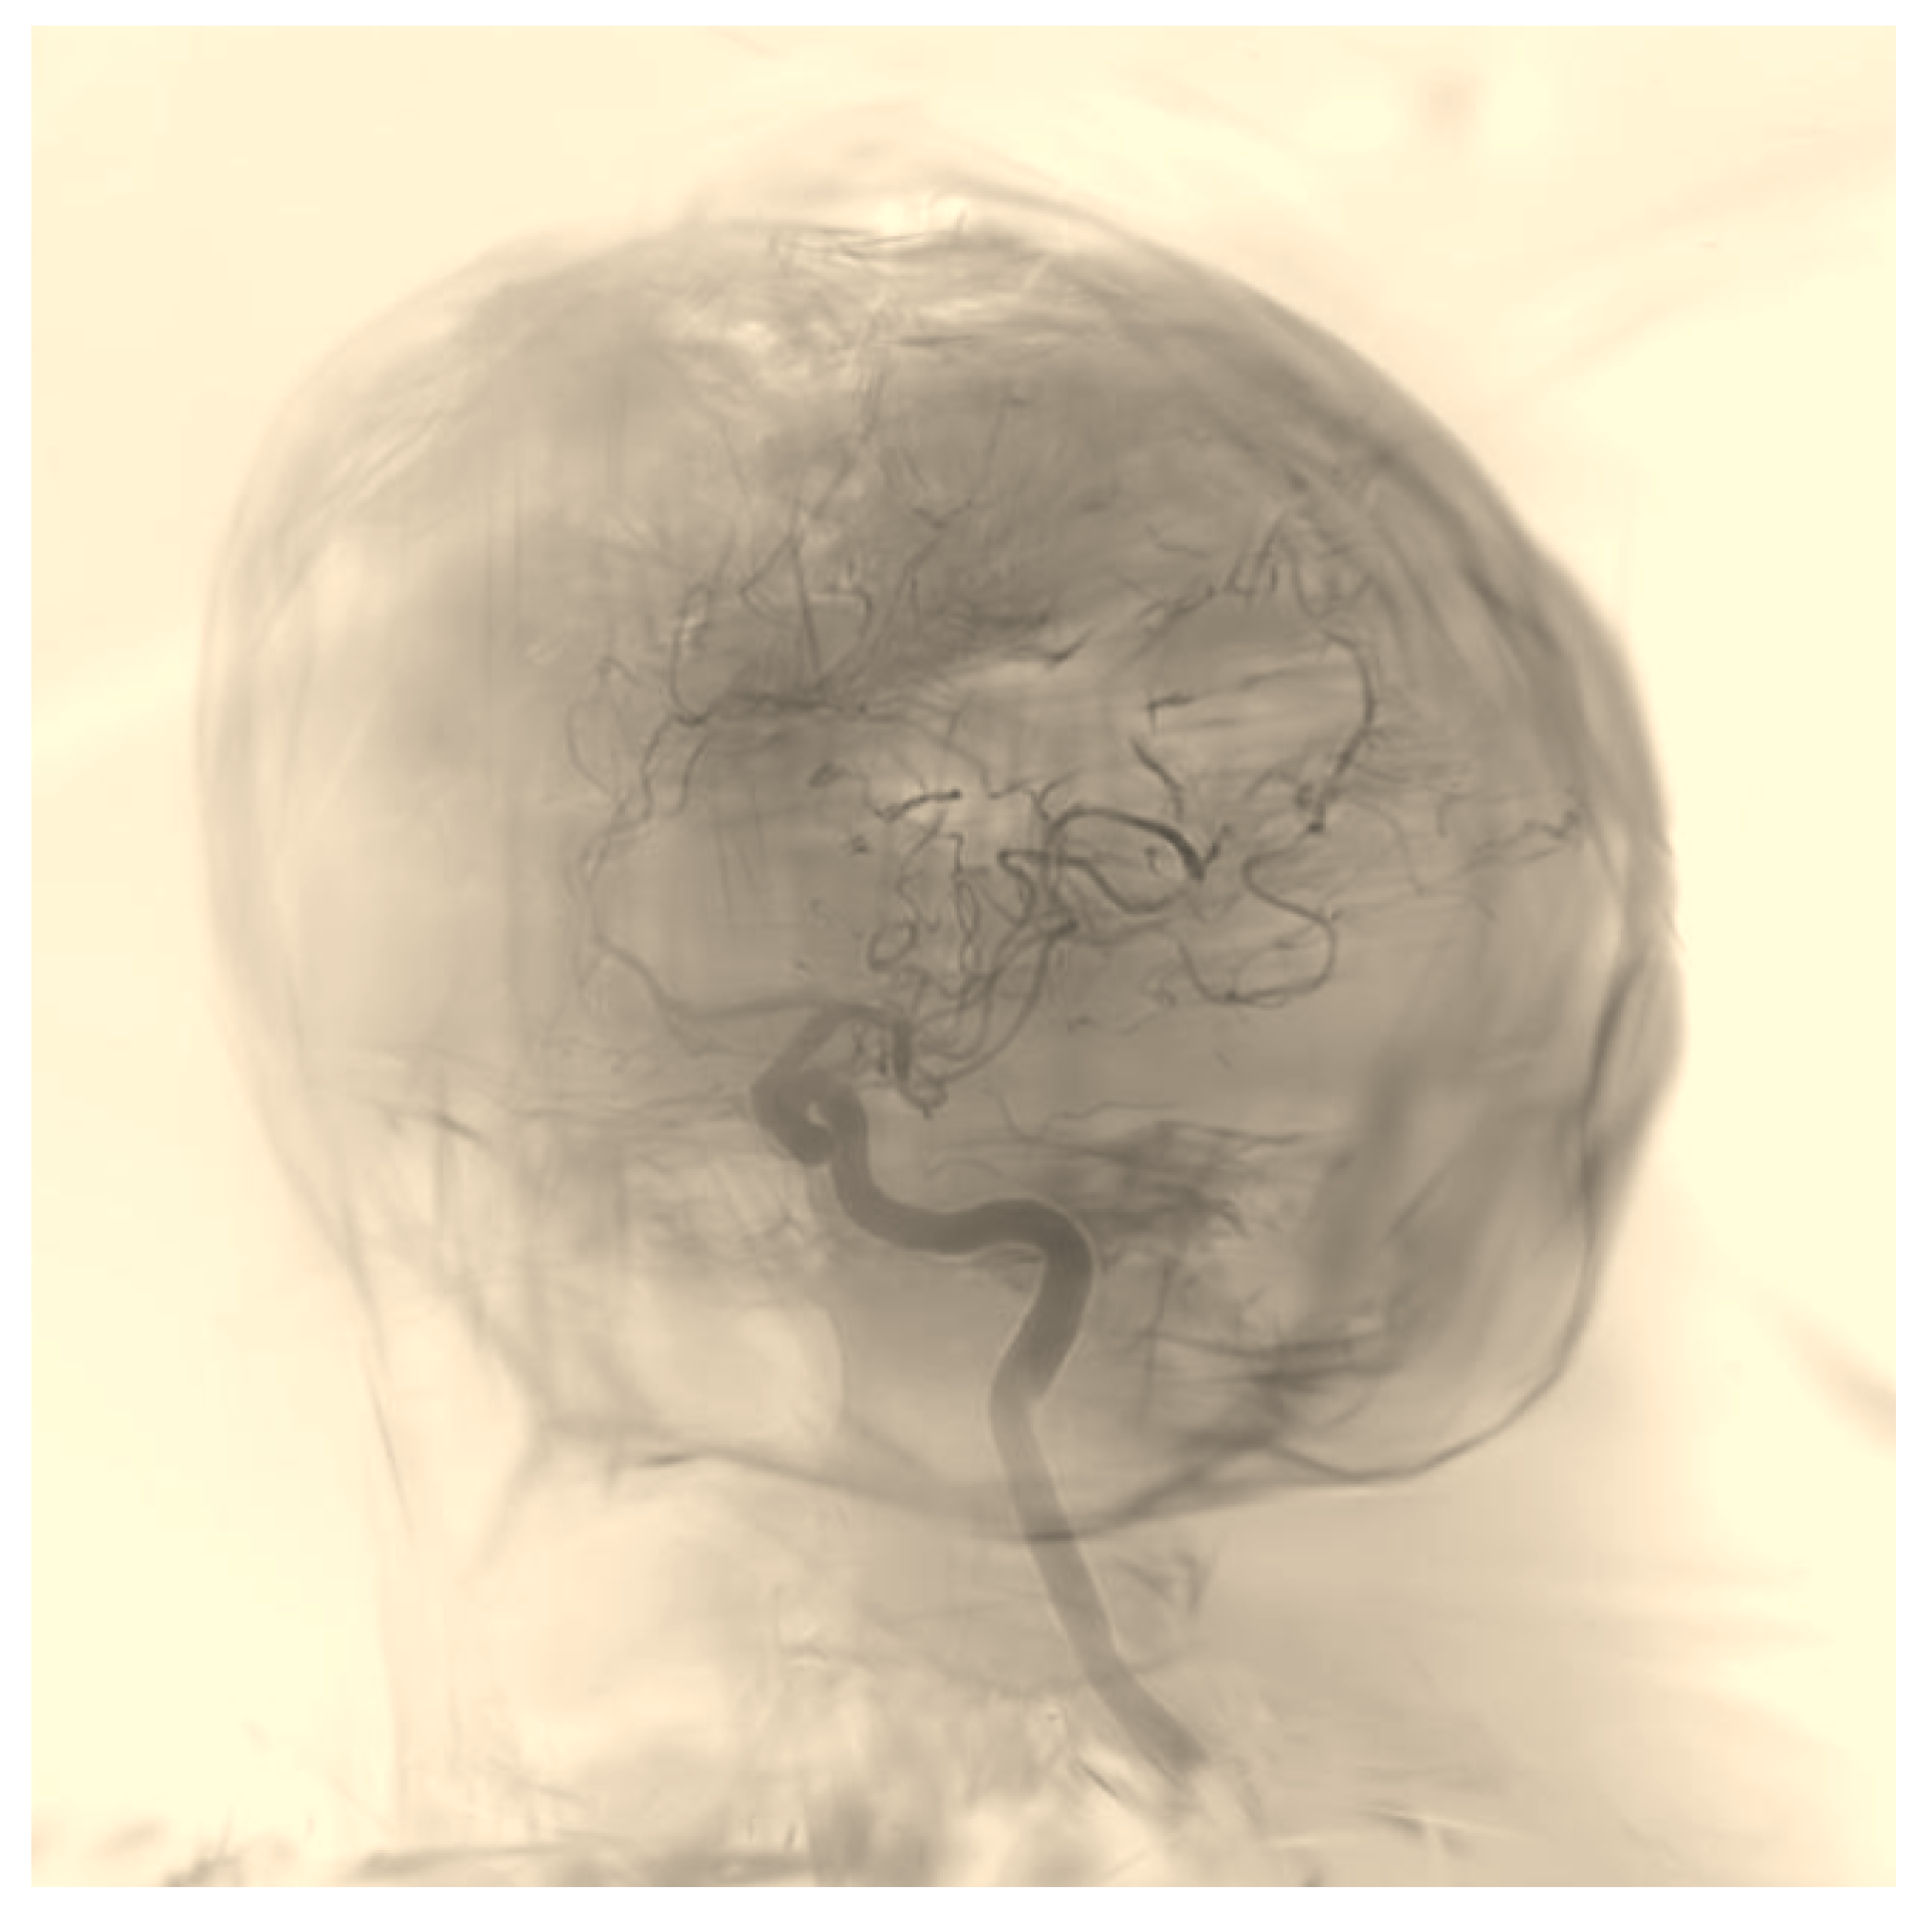

2.3.3. Dataset Description

The training and evaluation process utilized datasets from two individual patients (Figure 1), each comprising 122 angiographic images. For training the nnU-Net model, we used the first patient dataset with fully annotated images, which were manually segmented by our team. This dataset was split into training and validation subsets and served as the primary source for model development. In total, the full training dataset contained 273 images, including DSA images from publicly available datasets and images from the first patient. A separate portion of the data, fully processed and anonymized, was reserved as an independent test case to ensure unbiased performance evaluation.

Figure 1. Example angiographic frames from the two patient datasets used for nnU-Net training and evaluation.